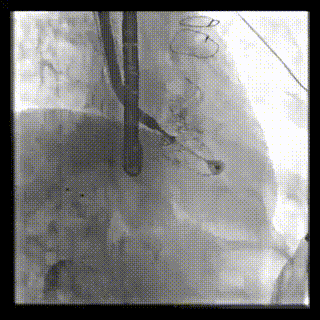

2021年12月24日,復(fù)旦大學(xué)附屬中山醫(yī)院葛均波院士團(tuán)隊成功應(yīng)用LuX-Valve Plus為一例極重度三尖瓣反流(TR)合并房顫、房缺的患者完成了經(jīng)血管三尖瓣置換術(shù),這是在前基礎(chǔ)上,本周完成的第三例經(jīng)血管三尖瓣置換手術(shù),葛均波院士、周達(dá)新教授等與心外科魏來教授、賴顥教授,心超室的潘翠珍教授、李偉教授及麻醉科的郭克芳教授共同完成了本周手術(shù),均獲得圓滿成功!患者術(shù)后超聲顯示無TR,臨床癥狀明顯改善。本周手術(shù)的成功也為LuX-Valve Plus救治性臨床研究添上了濃墨重彩的一筆。

本周三例接受LuX-Valve Plus經(jīng)血管三尖瓣置換術(shù)的患者中,第一例患者為冠狀動脈旁路移植術(shù)+Bentall+二尖瓣成形術(shù)后;第二例患者為永久起搏器植入術(shù)后,存在跨三尖瓣導(dǎo)線;第三例患者合并房顫、房缺及左心耳封堵術(shù)后。

三例患者入院后,葛均波院士團(tuán)隊周達(dá)新教授、潘文志教授、張源博士、陳莎莎博士及心超室的潘翠珍教授、李偉教授對患者的情況進(jìn)行詳細(xì)評估和討論,最終決定為三例患者選擇LuX-Valve Plus40mm、50mm和50mm型號的瓣膜進(jìn)行手術(shù)治療。手術(shù)后即刻拔除氣管插管,術(shù)后患者三尖瓣反流癥狀得到顯著改善,復(fù)查心超結(jié)果顯示人工三尖瓣瓣膜支架固定穩(wěn)定,瓣葉關(guān)閉形態(tài)未見異常,未見明顯反流。